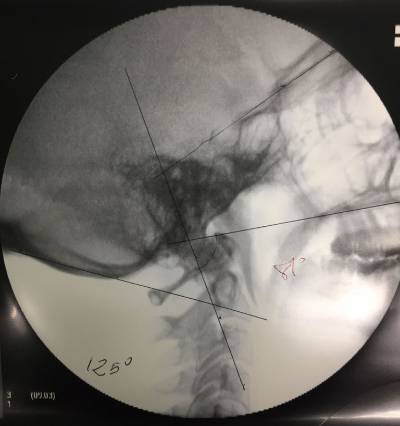

Once in the Operating Room, surgery is performed under general anesthesia, with Neurophysiological monitoring (SSEP – somatosensory evoked potentials), neuronavigation guidance and intraoperative fluoroscopy guidance.

Thus we control spinal cord and nerves (cranial and cervical) in order to avoid potential damages to these important structures. Neuronavigation assistance guides us all through the surgery, thus it diminishes (though it does not eliminate) the risks while placing the screws for the fusion. Both neurophysiological monitoring and neuronavigation guidance are safety measures for the patient.